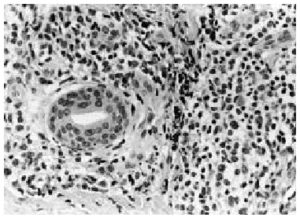

Se realizó una biopsia de la lesión cutánea (fig. 2), que demostró una infiltración perivascular superficial y profunda y perianexial por grupos de células grandes con gran desproporción núcleo-citoplasmática, citoplasma amplio eosinofílico y núcleo irregular con nucléolo prominente (fig. 3), siendo sugestiva de infiltración por LMA.

Fig. 2.--Imagen panorámica en la que se observa en la dermis reticular una infiltración multinodular por células leucémicas.